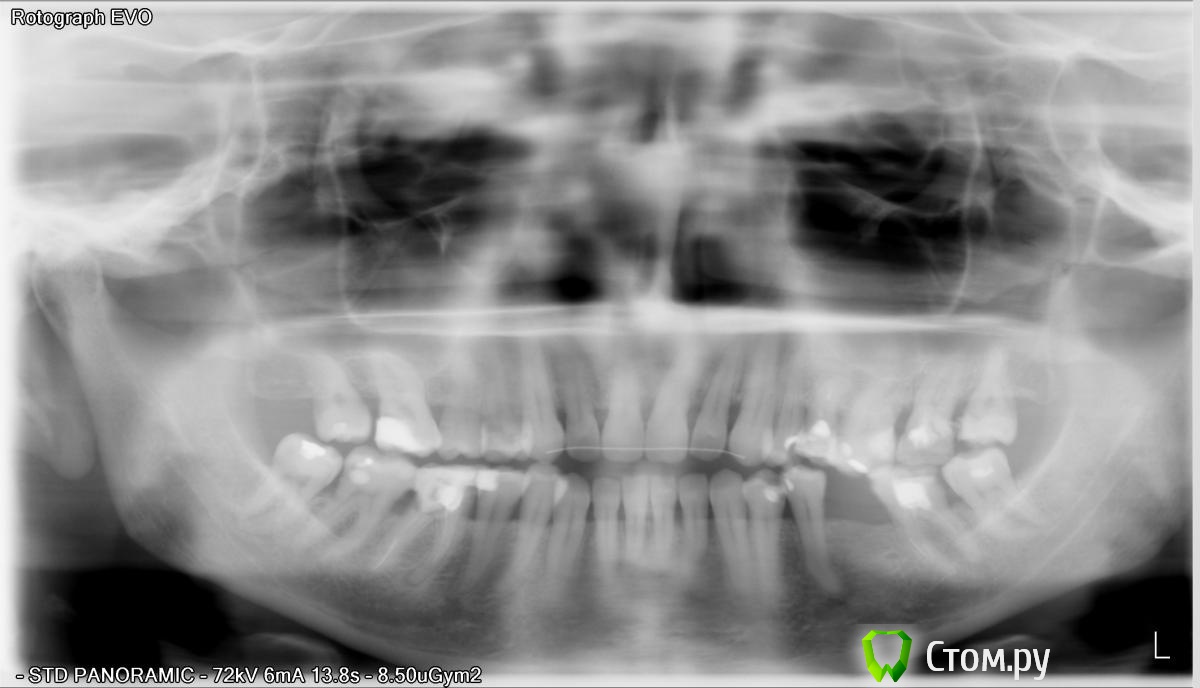

Art 7 Опубликовано 9 января, 2014 Поделиться Опубликовано 9 января, 2014 Добрый день, Состояние в полости рта усугубляется отсутствием двух зубов, одного на верхней челюсти справа и одного на нижней челюсти слева. Из-за их отсутствия зубы сместились и межзубные контактные пункты уже не плотные, пища травмирует десну и поддерживает воспаление. Так как снимок не качественный не берусь утверждать какие зубы надо перелечивать, напишу лишь списком на какие зубы необходимо обратить внимание1.7. 2.4. 2.5. 2.6. 2.7. 2.83.7. 3.5. 4.6. Восстановление отсутствующего зуба на нижней челюсти обязательно. В общем лучше будет если Вы сделаете качественный снимок, а лучше сразу сделать компьютерную томограмму и найдёте грамотного специалиста ортопеда, который всё спланирует, так как здесь необходима совместная работа терапевта, ортодонта, хирурга, и ортопеда. Ссылка на комментарий